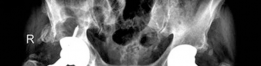

Revision THA Acetabulum Paprosky Type IIIA. ARMD with Metallosis with Severe Periacetabular Osteolysis and Co…

Case Title: Acetabular Augment for Acetabular Bone Deficiency Demographics Age: 80 years Sex: Female BMI: 27 …

Case Title: Acetabular Impaction Grafting Demographics Age: 79 Sex: female BMI: 22 Relevant Past Medical Hist…

Case Title: Acetabular Augment for a Paprosky Type IIIA Acetabular Defect Demographics Age: 67 years Sex: Mal…